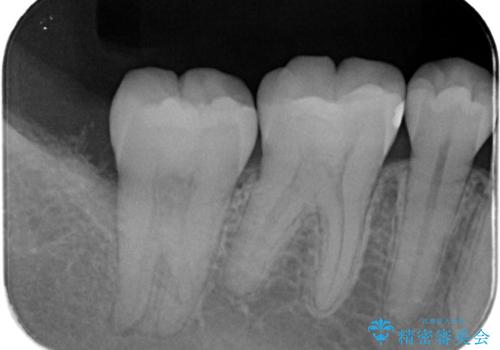

レントゲン写真は、処置後一年経過時のもので、歯周ポケットは遠心4mm、舌側3mmまで減少、出血なし。

一度目の再生療法でできる骨形態は移行的でないこともあるため、経過を診つつ骨整形も必要であれば今後行う予定です。